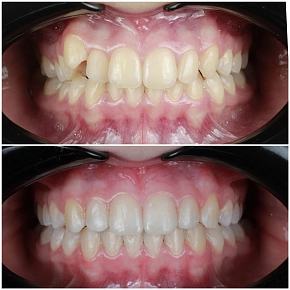

Как подбирается форма будущих виниров?